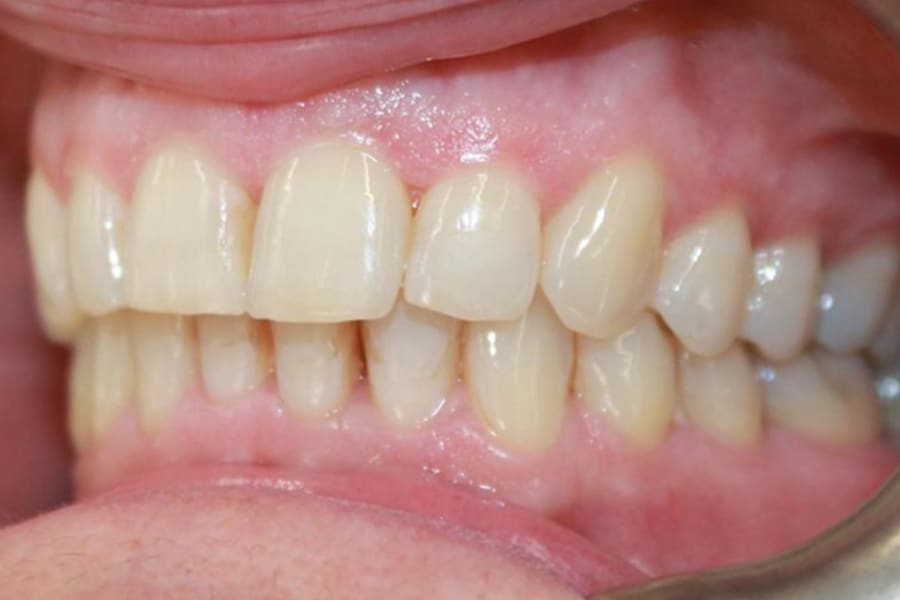

A 54-year-old woman presented with a chief complaint of teeth crowding. After comprehensive digital records were obtained, ClearCorrect® aligner therapy (Straumann, clearcorrect.com) was chosen with an anticipated 12-month treatment duration. The patient exhibited moderate anterior crowding, a class II molar relationship, and narrow arches. The treatment plan aimed to resolve the class II discrepancy, expand the arches, and establish proper anterior alignment. A total of 25 active aligners plus two retention aligners were prescribed. Attachments were selectively placed on the maxillary and mandibular canines to premolars, minimizing bulk while maintaining control over torque and posterior alignment. The patient was instructed to wear class II elastics full-time, which was crucial to achieving molar correction and arch expansion. Her outstanding compliance with class II elastics contributed to a significant improvement in molar position and transverse arch development. After completing the active phase, the patient transitioned to retainers to ensure long-term stability of the results. Given the patient’s initial class II occlusion, monitoring retention was emphasized to prevent relapse. The patient was extremely pleased with the outcome, demonstrating a broadened smile and improved occlusal function. This case underscores the effectiveness of ClearCorrect’s aligners in adult patients, particularly when combined with compliant elastic wear and targeted expansion strategies.